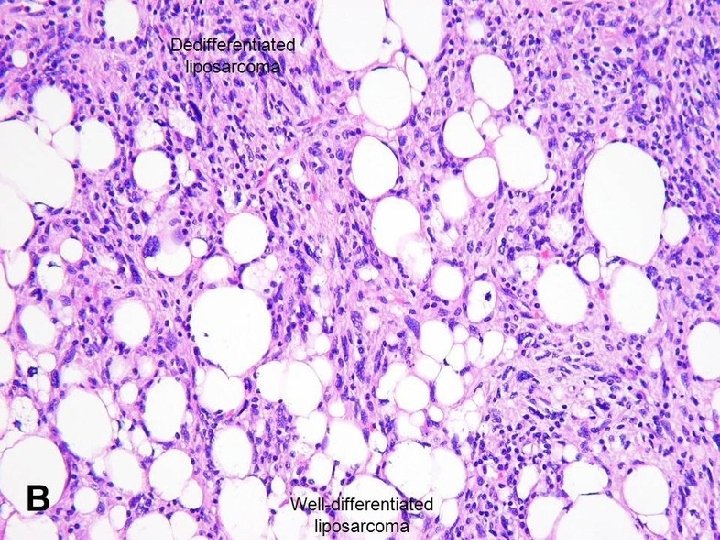

Liposarcoma Malignant neoplasms of adipocyte. Most common in fifth & sixth decades of life. Arise in deep soft tissues or in retroperitoneum. Well-circumscribed lesions. Morphology: Several different histologic subtypes: 1 - Well-differentiated liposarcoma. 2 - Myxoid/round cell liposarcoma: Characterized by abundant mucoid extracellular matrix. 3 - Poorly differentiated tumors.

Prognosis is influenced by the Histologic subtype: Well-differentiated tumors: q Grow slowly. q Associated with more favorable outlook. q Have Good prognosis. Myxoid/round cell & poorly differentiated tumors q. Aggressive tumors. q. Recur after excision. q. Have Poor prognosis.

Well-differentiated liposarcoma.